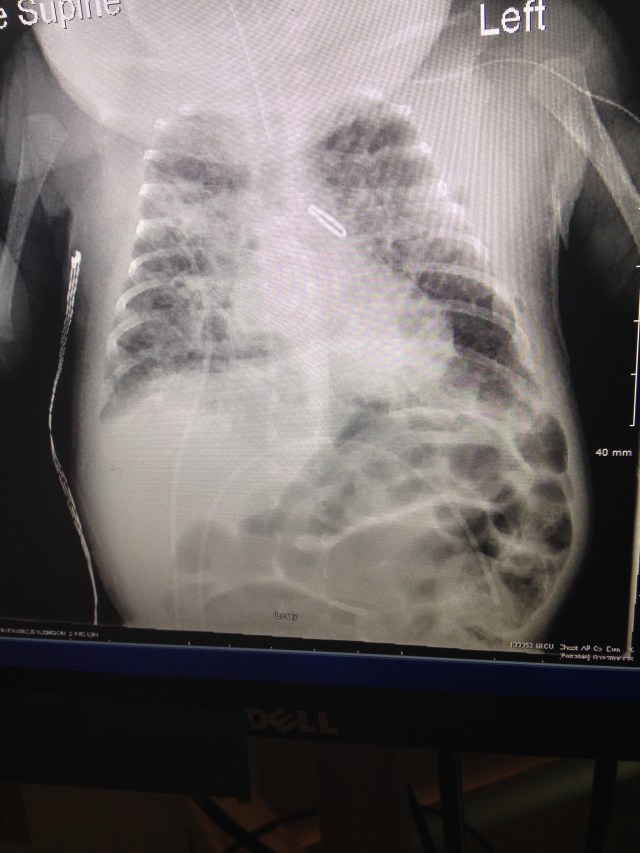

Nurse says RT did good, they have the xray complete so we ask to see it. I do like pictures.

Dr. Comes in and talks to us about the xray, tells us RT did as well as he could. Xray looks good. For now, no complications presenting themselves from surgery.

X-ray shows clip holding PDA shut.